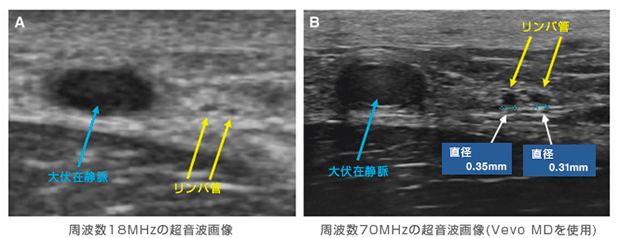

<周波数の違いによる超音波画像の見え方の比較>(*6)

下腿体表付近の2本のリンパ管(黄矢印)と,静脈 (青矢印)を,周波数18MHzの超音波プローブと70MHzの超音波プローブ(Vevo MD)で,観察・比較したもの。周波数70MHzのプローブの画像(右側:画像(B))では,直径約0.3mmのリンパ管が明瞭に描出されている。

*6 参考文献:Hayashi A, et al. Ultra High-frequency Ultrasonographic Imaging with 70 MHz Scanner for Visualization of the Lymphatic Vessels. Plast Reconstr Surg Glob Open 2019;7:e2086.